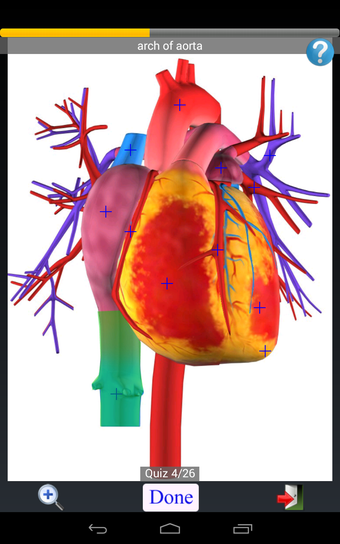

Anatomy Quiz Free es una aplicación de Android de Education Mobile que ofrece una amplia gama de cuestionarios para ayudar a los usuarios a aprender anatomía humana. La aplicación cuenta con más de 500 cuestionarios que ponen a prueba tu capacidad para identificar la ubicación correcta de un objeto dado su nombre. Los cuestionarios se generan a partir de modelos de anatomía 3D virtuales, lo que los hace más atractivos e interactivos. La aplicación es gratuita y no hay versiones premium ni compras dentro de la aplicación.

La aplicación es compatible con los idiomas inglés, francés, español y alemán, lo que la hace accesible para usuarios de diferentes partes del mundo. Las imágenes de alta resolución son nítidas y claras, y la función de zoom con pellizco te permite acercar y alejar las imágenes para una mejor vista. El cuestionario de posición viene con un temporizador, lo que lo hace más desafiante y emocionante. Además, la aplicación tiene una función de transferencia a la tarjeta SD, lo que facilita su transferencia a otros dispositivos.